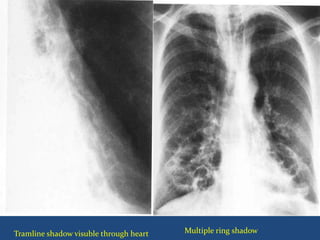

 Chest radiographs:

 Tram tracks parallel line opacities

 Ring opacities

 Tubular structures.

 X ray photo

Multiple ring shadowTramline shadow visuble through heart